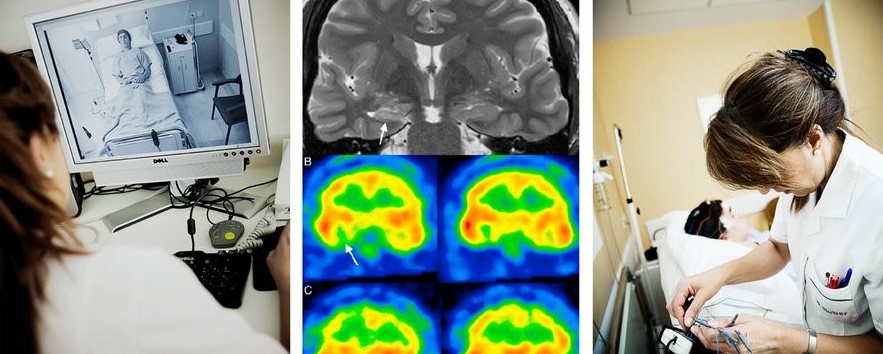

Unidad de Epilepsia del Hospital Ruber Internacional de Madrid

Antonio Gil-Nagel y Ángel Aledo del Hospital Ruber Internacional